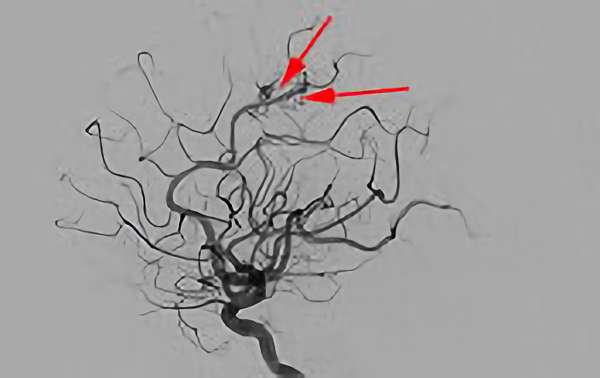

No.1576 手術前

No.1576 手術中

No.1576 手術後